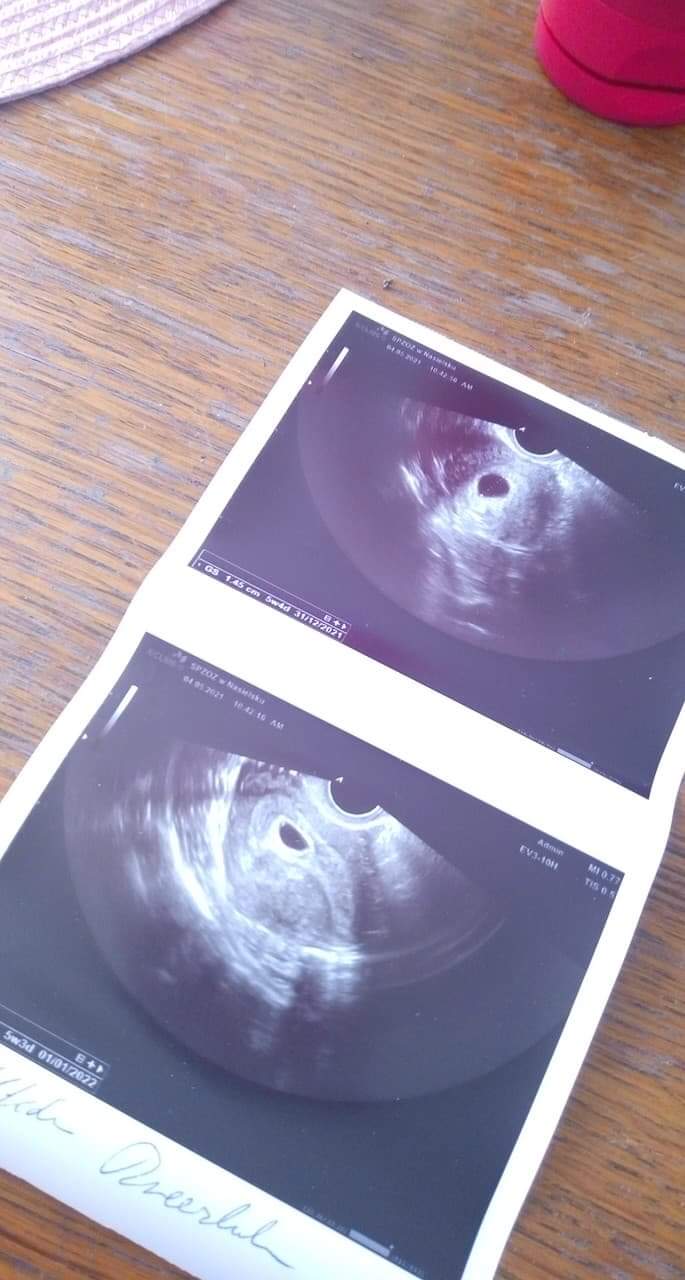

Jestem po ciąży pozamacicznej, która miała miejsce w lutym, 5 marca miałam ostatnią miesiączkę, 19 kwietnia ( licząc od OM był to 6 tydzień i 4 dzień) byłam u ginekologa który potwierdził ciążę w macicy, 2 pęcherzyki ciążowe, niestety nie dostrzegłam zarodków ani pęcherzyków żółtkowych, mój ginekolog nie mówi za dużo i nie udzielił mi nawet informacji który wg niego to tydzień, kiedy przewiduję termin porodu, dostałam tylko skierowanie na badania) bardzo mnie to zmartwiło, to moja pierwsza ciąża ( właściwie umiejscowiona), może któraś z Pań widzi coś na tym USG? Albo jest jeszcze za wcześnie by zobaczyć zarodek? Bardzo się martwię... Z góry dziękuję za odpowiedzi!

trzymam kciukiJestem po wizycie, lekarz powiedział że albo ciąża jest sporo młodsza albo puste jajo i w razie plamienia dał skierowanie do szpitala, wg USG wychodzi 5 tydzień i 4 dzień, pęcherzyki sporo urosły, bardzo się martwię...